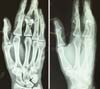

Nesta série de casos, os tipos de tratamento selecionado para ser utilizado nos pacientes variou de imobilização com gesso (1 caso - 3,8%); Placa Sistema 2.4 (3,8%); Fio de Kirschner + Conservador (3,8%); Cimento ósseo pela técnica de Masquelet (3,8%); Fio de Kirschner + Placa (3,8%); Placa Sistema 2.0 + amarris com Aciflex® (3,8%) (Figuras 1 e 2); Fixador externo + Sistema tipo Suzuki (3,8%); Fio de Kirschner (7,7%); fio de Kirschner com amarris Aciflex® (3,8%) e Placa sistema 2.0 (14 casos - 53,8%) (Figuras 3 e 4); Sistema tipo Suzuki (7,7%) (Figuras 5 e 6).

A maioria dos pacientes, correspondente a 22 casos (84,6%), não necessitou de utilização de retalho cutâneo para cobertura de lesões. Do total de pacientes, 18 realizaram enxerto ósseo, dos quais 67% foram retirados do osso ilíaco. Dentre o surgimento de lesões associadas, a mais frequente foi a do aparelho extensor, acometendo 26,9% (7 pacientes) porém, de um modo geral, a maioria dos pacientes não sofreu com tais distúrbios.

A sequela mais prevalente foi a rigidez articular, acometendo 57% dos pacientes. Todos os pacientes receberam antibioticoterapia venosa terapêutica no momento do primeiro desbridamento na emergência até o dia da cirurgia e durante 7 dias, via oral. Foi usada cefalosporina de primeira geração. Não houve extrusões ou infecções de materiais de fixação rígida. Houve um caso de necessidade de troca de placa de titânio por motivo de quebra, visualizada em raio-x de controle em pós-operatório de 7 dias. Em relação ao tempo de acompanhamento dos pacientes, 12 (46,1%) não tiveram seguimento, 9 (34,7%) foram inferiores a 1 ano e 5 (19,2%) foram maiores ou iguais a 1 ano.